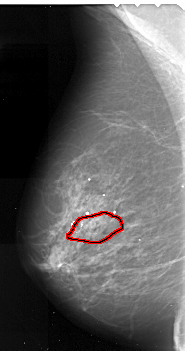

A_1049_1.LEFT_CC

FILE: A_1049_1.LEFT_CC.OVERLAY

TOTAL_ABNORMALITIES 1

ABNORMALITY 1

LESION_TYPE CALCIFICATION TYPE PLEOMORPHIC DISTRIBUTION SEGMENTAL

ASSESSMENT 4

SUBTLETY 3

PATHOLOGY MALIGNANT

TOTAL_OUTLINES 1

BOUNDARY